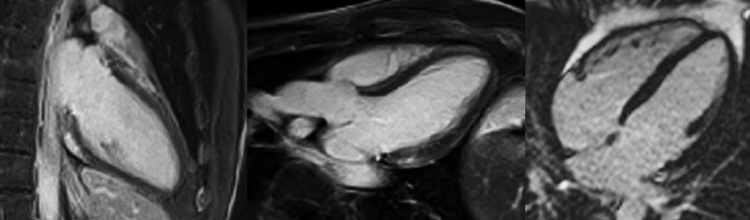

Figure 2 : Séquence cartographie T2 - Coupes petit-axe basal (A), médian (B) et apical (C)

Figure 5 : Séquence cartographie T2 - Coupes petit-axe basal (A), médian (B) et apical (C)

Présence d’une zone d’œdème myocardique inféro-latéro-basale avec une élévation importante du T2 mapping à 65 ms (norme < 50 ms), a fortiori bien supérieure à la valeur de T2 mapping du reste du myocarde, mesurée à 45 ms.

Astuce quant à l'analyse du T2 mapping

La séquence de T2 mapping permet de détecter la présence d’œdème myocardique selon deux méthodes possibles en pratique :

- une zone avec une valeur de T2 mapping myocardique ≥ 50-55 ms (norme < 50 ms).

- une zone avec une valeur de T2 mapping élevée comparativement à une zone myocardique saine.

Attention : l’œdème myocardique n’est pas spécifique de myocardite aiguë, mais peut aussi être présent pour un infarctus du myocarde, un syndrome de Takso-tsubo, une sarcoïdose, ou n’importe quelle maladie de système en poussée…